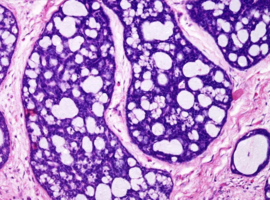

Coexistence of a Malignant Phyllodes Tumor of the Breast with Heterologous Elements (Osteosarcoma and Chondrosarcoma) and Invasive Ductal Carcinoma: Case Report and Review of the Literature

Ashjian N, Mehrabi C, Dickinson B*, et al. (USA)